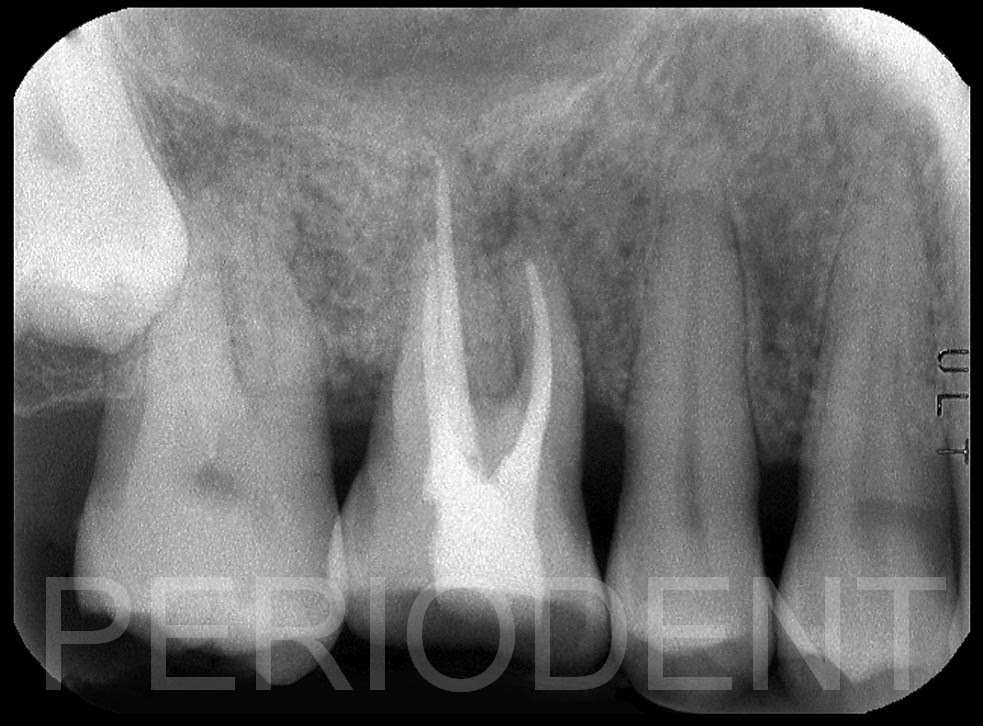

患者治療前,因為牙周問題導致牙齒神經壞死

根管治療後